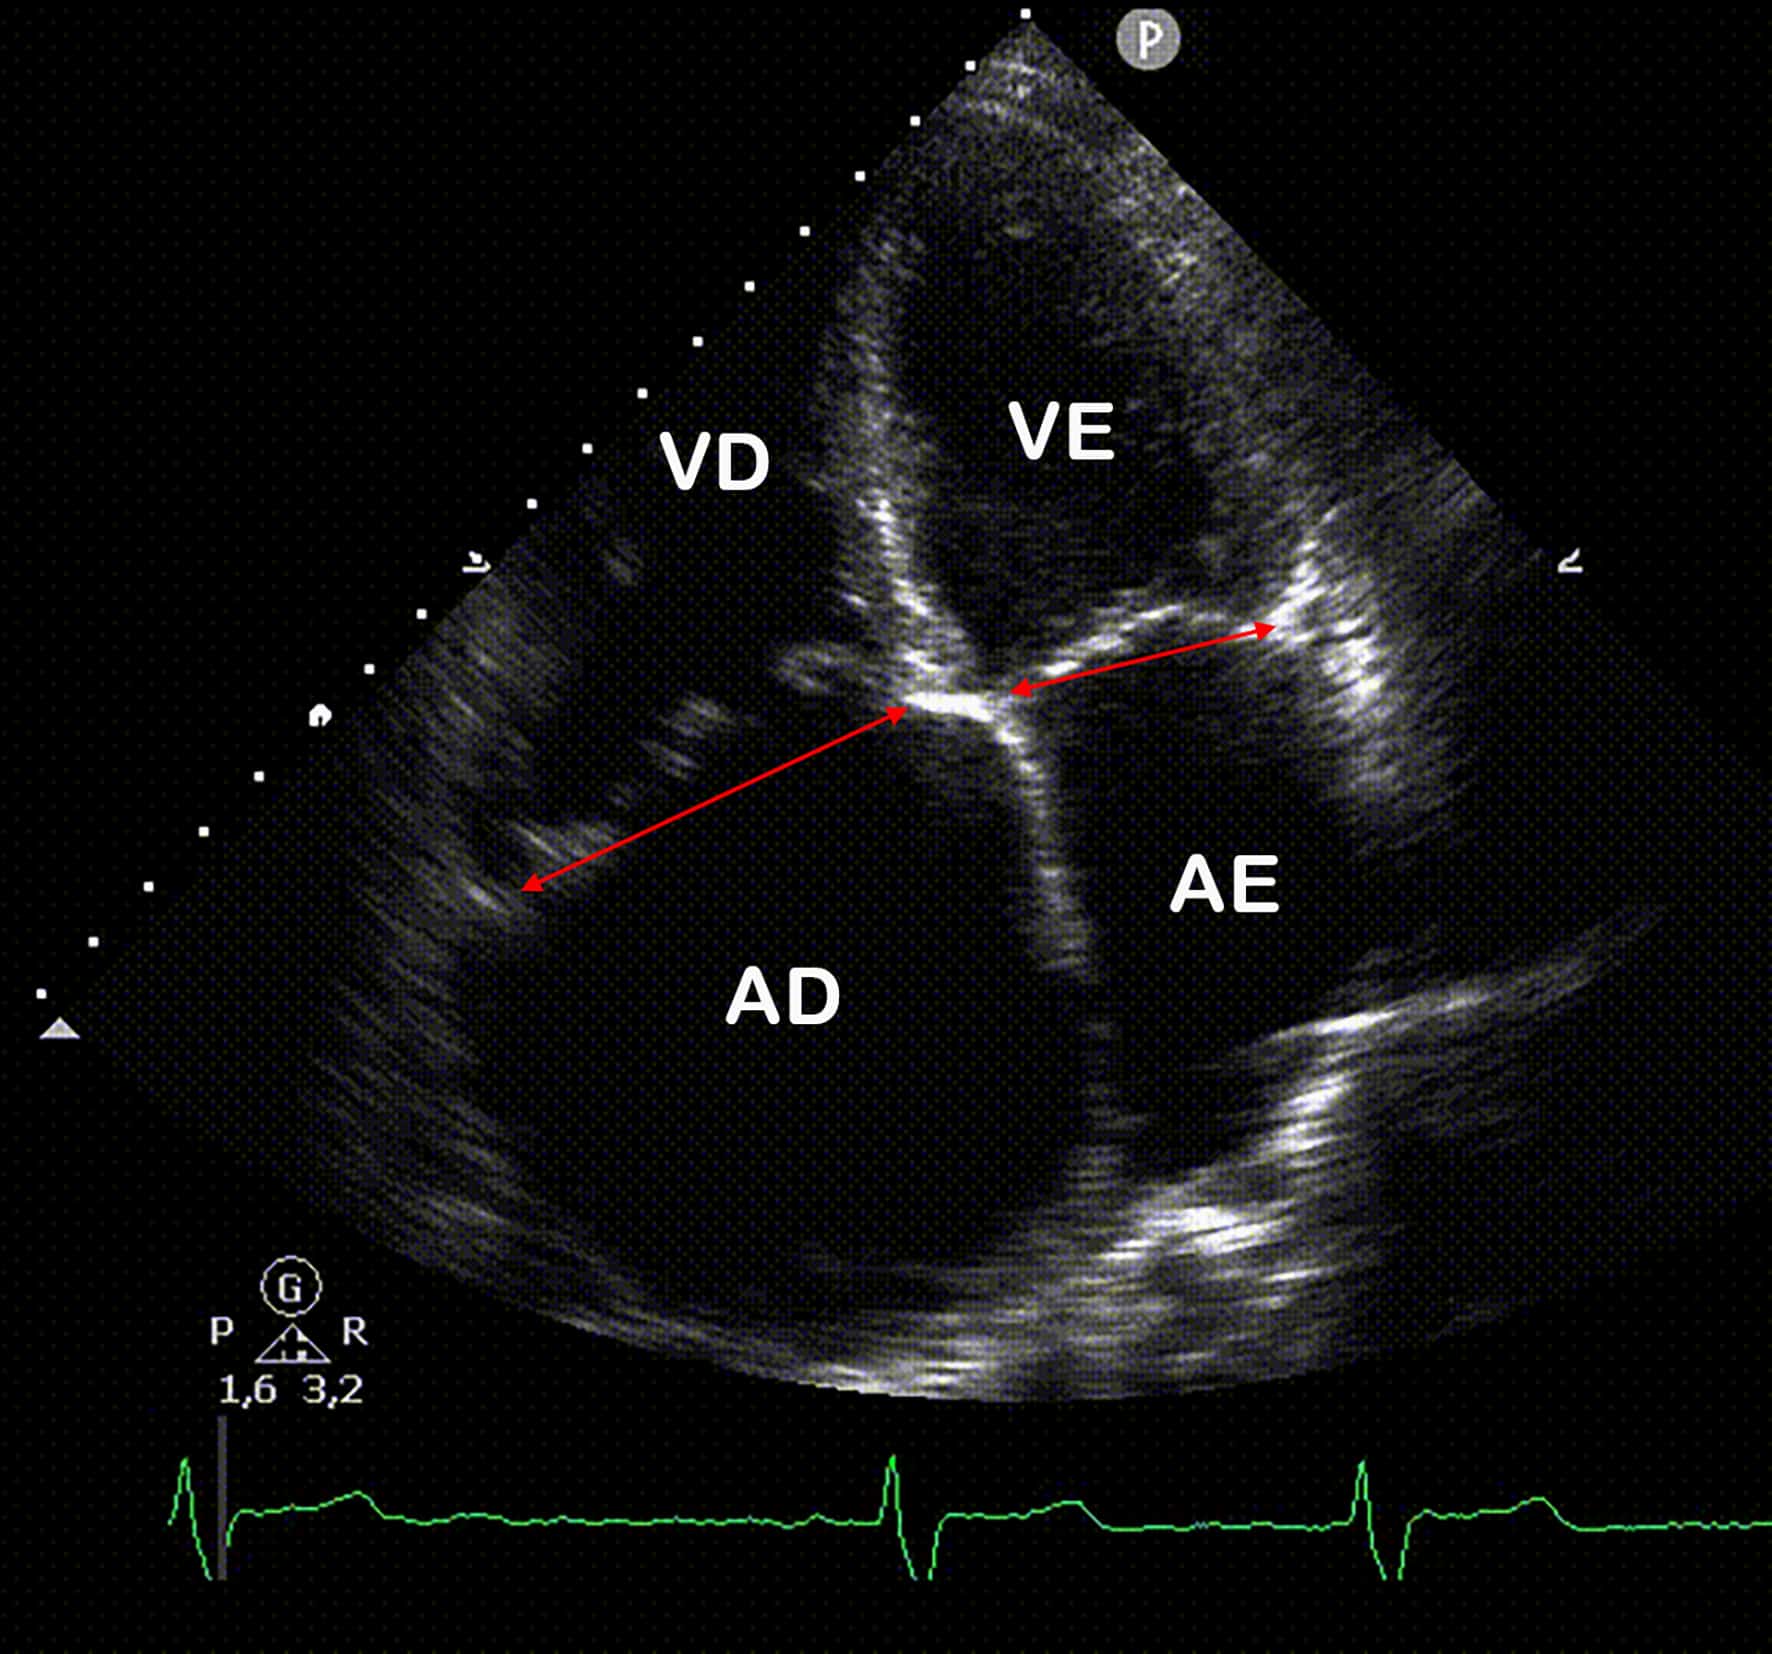

IDENTIFICAÇÃO ECOCARDIOGRÁFICA DA HIPERTENSÃO PULMONAR - Blog Ecope